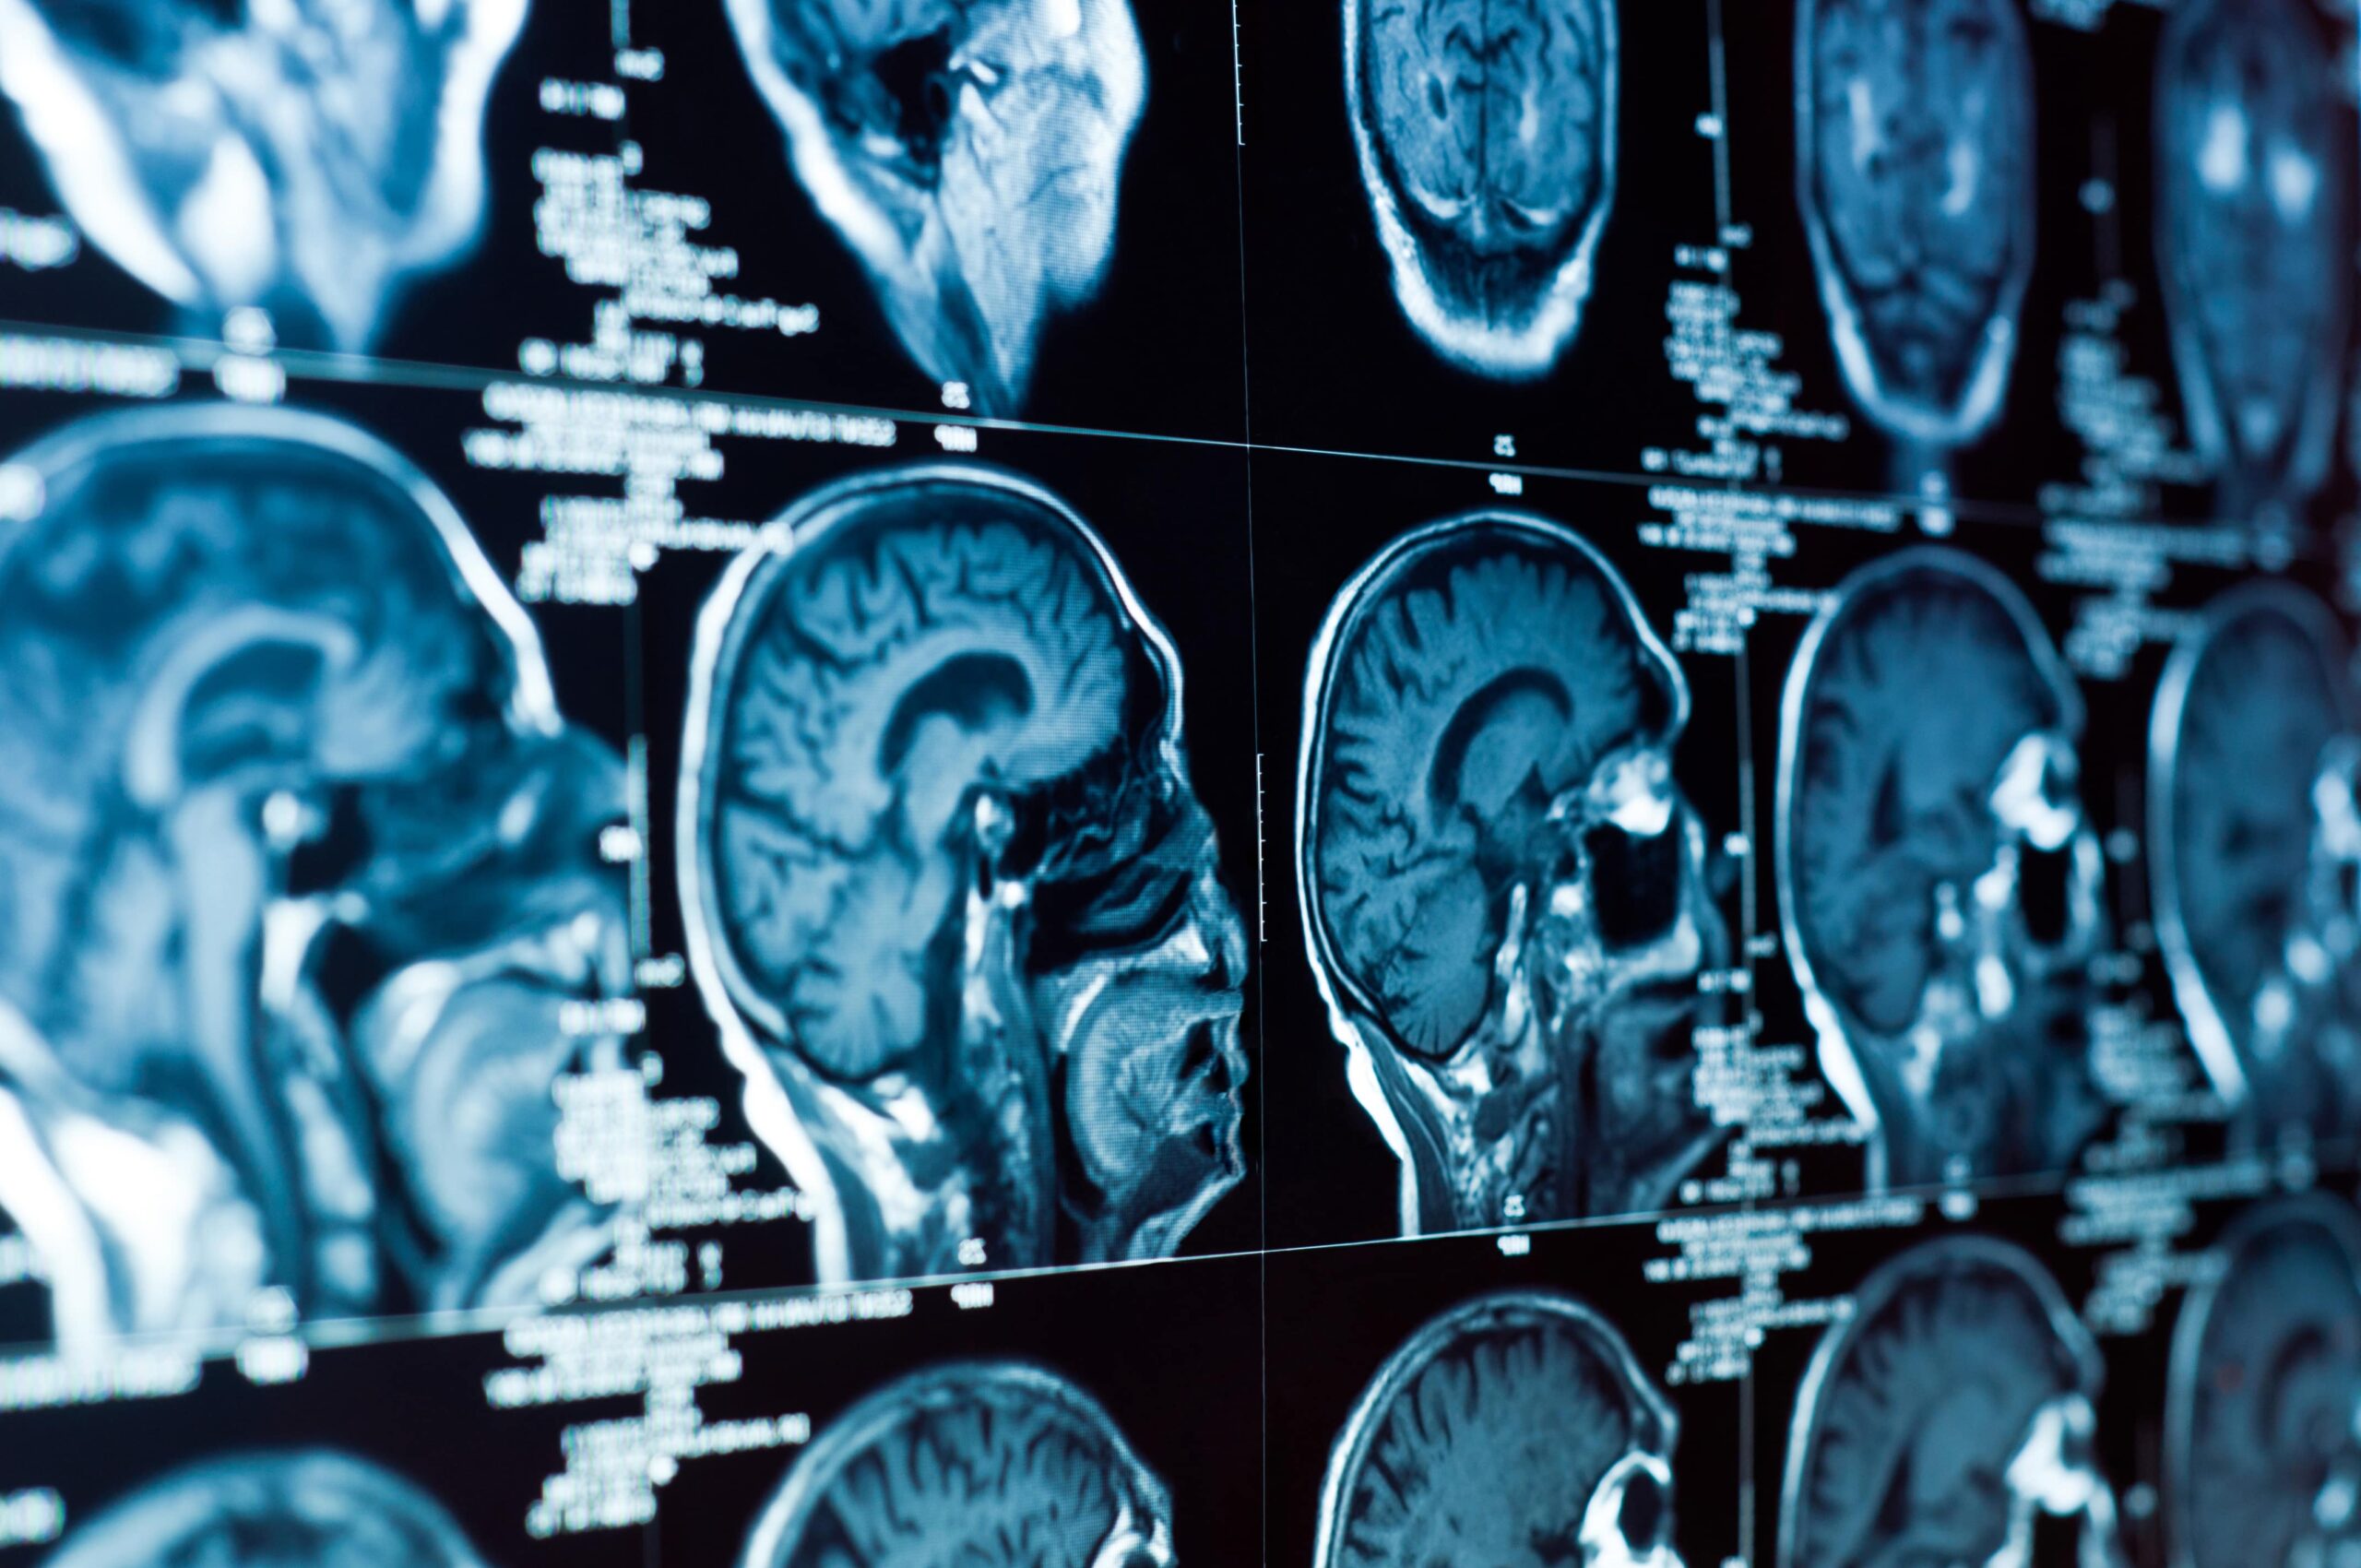

Sustaining a brain injury can be a life-altering event, not only for the victims but also for their families and loved ones. The road to recovery is often long and challenging, filled with medical treatments, therapy sessions, and adjustments to daily living. In Tulsa, there is a strong network of support available for brain injury victims, helping them navigate this difficult journey.

One of the critical first steps after sustaining a brain injury is seeking immediate medical attention. Timely and appropriate medical care can make a significant difference in the recovery process. Healthcare professionals in Tulsa are well-equipped to provide the necessary care and support, ensuring that patients receive the best possible treatment.

Rehabilitation is a crucial aspect of recovery, and Tulsa offers various rehabilitation centers specializing in brain injuries. These facilities provide tailored programs to meet the unique needs of each individual, helping them regain their independence and improve their quality of life.